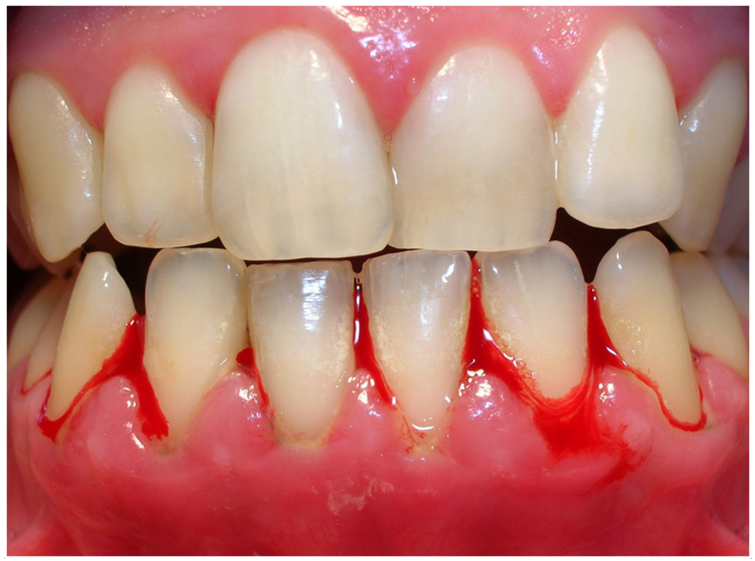

Bleeding Gums

Bleeding often happens during brushing, flossing, or sometimes even without touching the gums. This is a key sign of gum inflammation (Newman et al., 2022)

Gingival Inflammation and Redness

In the early stage, the gums become swollen, tender, and red because of inflammation caused by plaque buildup (Armitage, 1995; Newman et al., 2022).